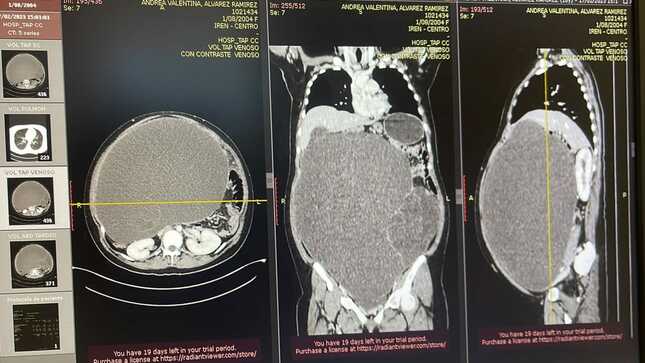

Un enorme tumor de 20 kilos de peso y de un metro de altura fue extirpado por los médicos especialistas del Instituto Regional de Enfermedades Neoplásica (IREN) centro, a la paciente Andrea Álvarez (18) natural del distrito de San Martín de Pangoa, en Junín. El tamaño de la tumoración que cubría todo el abdomen era similar a una mujer gestante de gemelos.

El médico Danilo Baltazar, subespecialista en ginecología oncológica, realizó la intervención quirúrgica luego que se realizaran todos los exámenes preoperatorios en tiempo récord. “Con éxito se extrajo la tumoración abdomino pélvica gigante con áreas quísticas y sólidas, y se envió a estudios patológicos”, refirió el galeno.